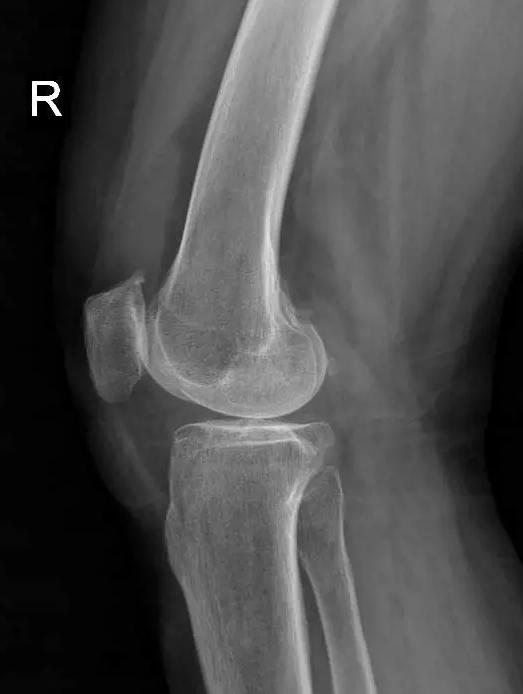

术前片:

对于晚期(重度)骨关节炎,保守治疗无效时,要积极考虑手术治疗。目前效果最佳的手术方式即为关节置换手术,其他手术方式如关节融合手术等效果较关节置换术相差较大,已不在临床广泛使用。关节置换手术的目的是缓解患者疼痛,矫正关节畸形,恢复关节功能,恢复正常生活。对于老年人来说,积极的手术治疗可以有效恢复其日常生活,避免因疼痛及活动障碍导致患者扶拐或坐轮椅,有效减少因缺乏运动导致的心肺功能障碍及精神问题发生。经过几十年的发展,目前关节置换技术已十分成熟,临床上目前采用的微创技术,手术创伤小,术中出血非常少,术后第二天患者即可下地行走,三月之后即可恢复正常生活及功能。至于人工假体使用寿命,目前进口关节多为20-30年,能满足60-70岁患者的需求。需要关注的是,在行关节置换手术之后,患者仍需要进行积极的康复治疗,包括关节活动度及周围肌力的锻炼等,这样才能达到最佳的手术效果。

晚期:骨关节炎表现为膝关节明显疼痛,休息后常无缓解,伴有活动受限,可并发畸形,X 线片可见关节周围有明显的骨赘形成,或可见游离体,关节间隙明显狭窄,甚至消失。